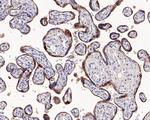

WB IHC IHC (P) IHC (PFA) IHC (F) ICC/IF IP ChIP IM

WB IHC IHC (P) IHC (F) ICC/IF Flow RIA